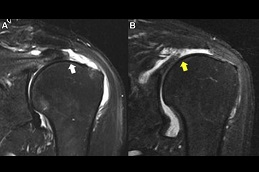

Results:

best prp-injection-for-rotator-cuff-tear in dubai prp injection for rotator cuff tear in dubai prp-injection-for-rotator-cuff-tear in Abu Dhabi

prp-injection-for-rotator-cuff-tear Clinic in Dubai Best prp-injection-for-rotator-cuff-tear Clinic in Dubai Best prp-injection-for-rotator-cuff-tear in Abu Dhabi